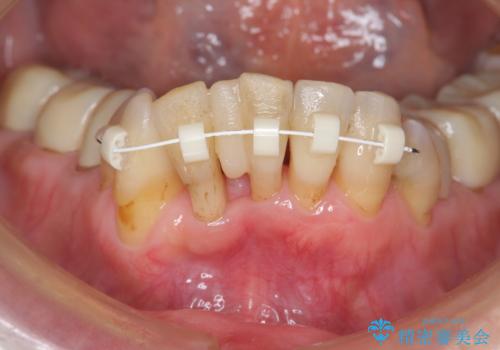

銀歯を高強度の仮歯に替えたのち、下顎前歯のみの部分矯正→全体的なマウスピース矯正治療(インビザライン)→最終的なセラミック治療と治療を進めます。

矯正治療と目立つ銀歯のやりかえを行ったことでかみあわせだけでなく、審美性・清掃性も改善し口腔内の環境を劇的に改善することができました。